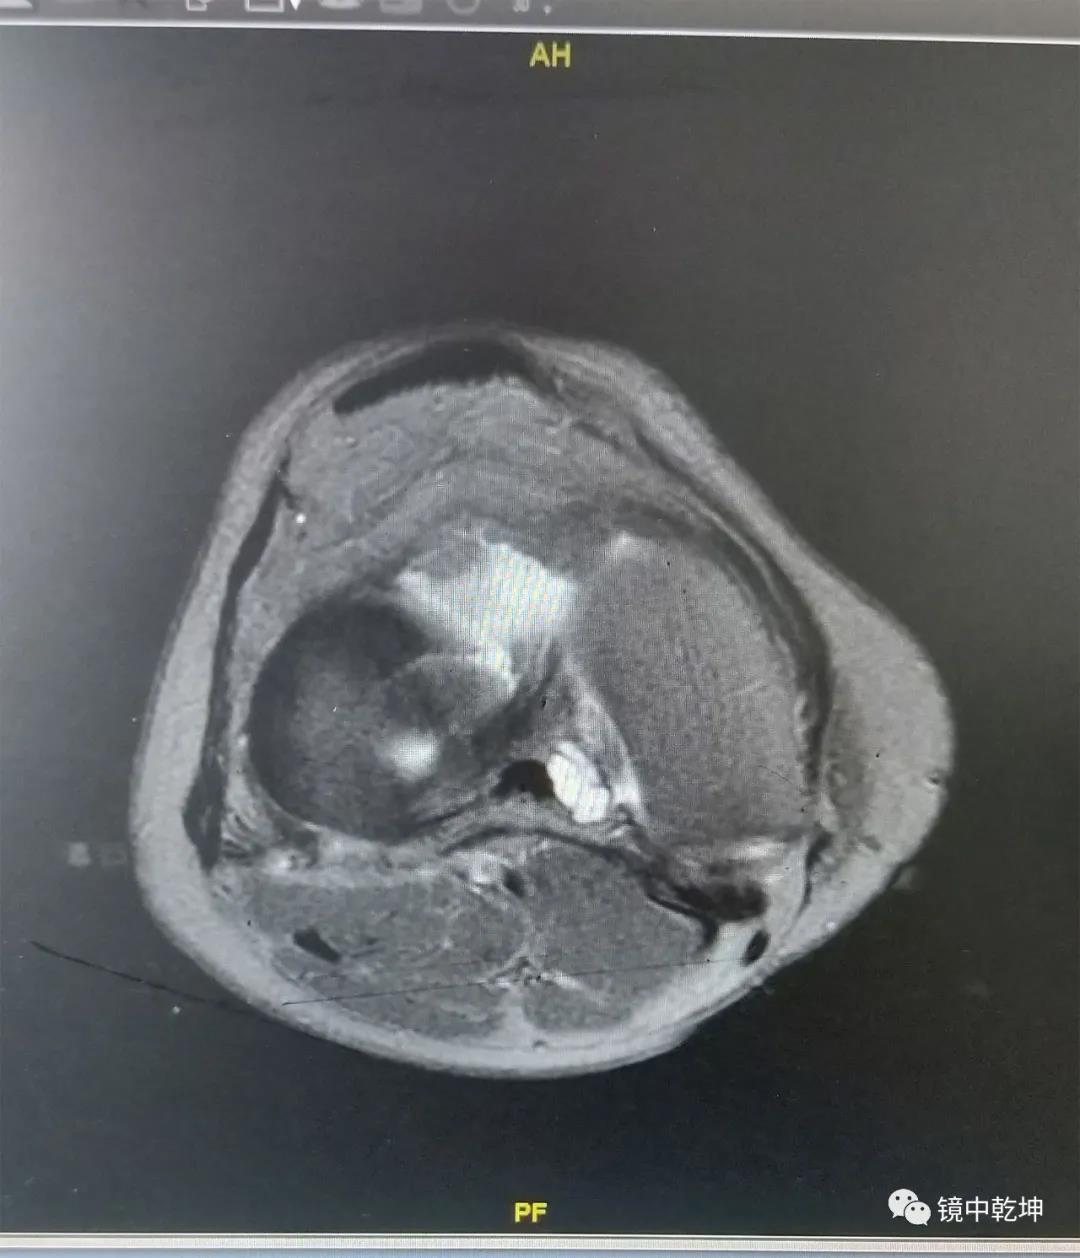

患者陈女士的MRI检查:

南昌大学第二附属医院骨科专家郝亮博士,李晨博士结合陈女士病情,诊断为半月板撕裂伤,并制定了手术方案。